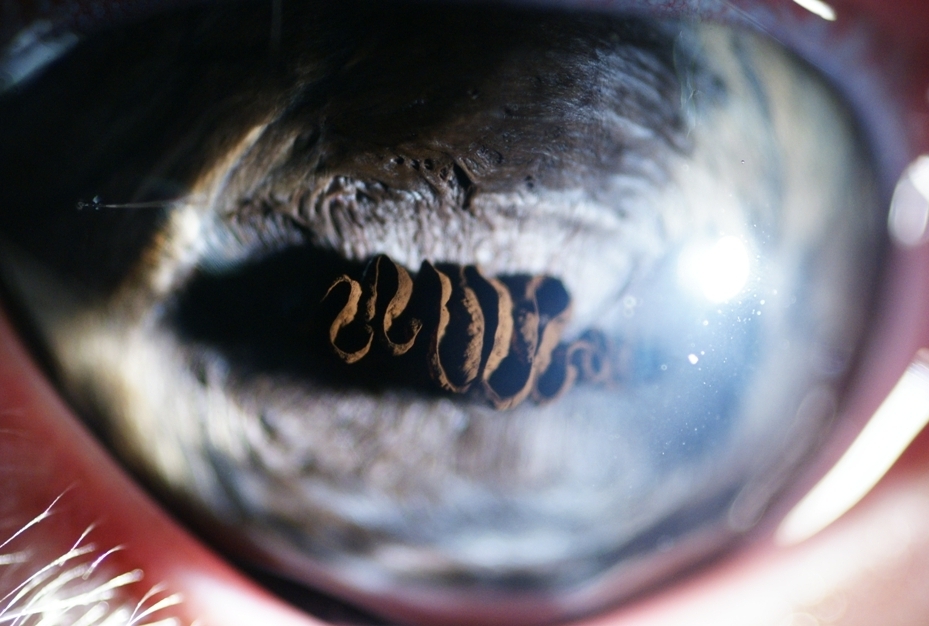

Le même vu de face. Le truc bizarre qui ressemble à du Vienetta s'appelle des grains de suie ou

Corpora Nigra. Théoriquement ça leur permet de filtrer la lumière.